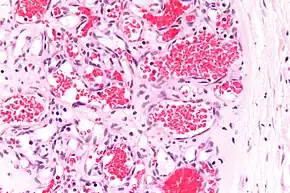

Capillary hemangioma

A precise history of the growth characteristics of the IH can be very helpful in making the diagnosis. In the first 4 to 8 weeks of life, IHs grow rapidly with primarily volumetric rather than radial growth. This is usually followed by a period of slower growth that can last 6–9 months, with 80% of the growth completed by 3 months. Finally, IHs involute over a period of years.[24] The exceptions to these growth characteristics include minimally proliferative His, which do not substantially proliferate[23] and large, deep IHs in which noticeable growth starts later and lasts longer.[24] If the diagnosis is not clear based on physical examination and growth history (most often in deep hemangiomas with little cutaneous involvement), then either imaging or histopathology can help confirm the diagnosis.[21][25] On Doppler ultrasound, an IH in the proliferative phase appears as a high-flow, soft-tissue mass usually without direct arteriovenous shunting. On MRI, IHs show a well-circumscribed lesion with intermediate and increased signal intensity on T1- and T2-weighted sequences, respectively, and strong enhancement after gadolinium injections, with fast-flow vessels.[21] Tissue for diagnosis can be obtained via fine-needle aspiration, skin biopsy, or excisional biopsy.[26] Under the microscope, IHs are unencapsulated aggregates of closely packed, thin-walled capillaries, usually with endothelial lining. Blood-filled vessels are separated by scant connective tissue. Their lumina may be thrombosed and organized. Hemosiderin pigment deposition due to vessel rupture may be observed.[27] The GLUT-1 histochemical marker can be helpful in distinguishing IHs from other items on the differential diagnosis, such as vascular malformations.[22]